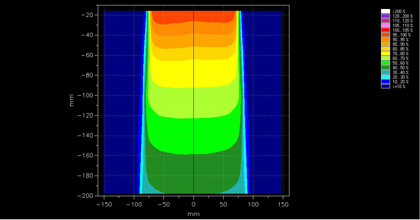

Shielding Calculations

Required by regulatory agencies, appropriate shielding for your equipment including linear accelerator, diagnostic, and PET imaging is extremely important. Following the newest NCRP recommendations, OMPC works WITH your design team to shield appropriately the simplest to the most interesting design applications. We feel there is ALWAYS a solution to incorporating good design with appropriate shielding in an economical way.